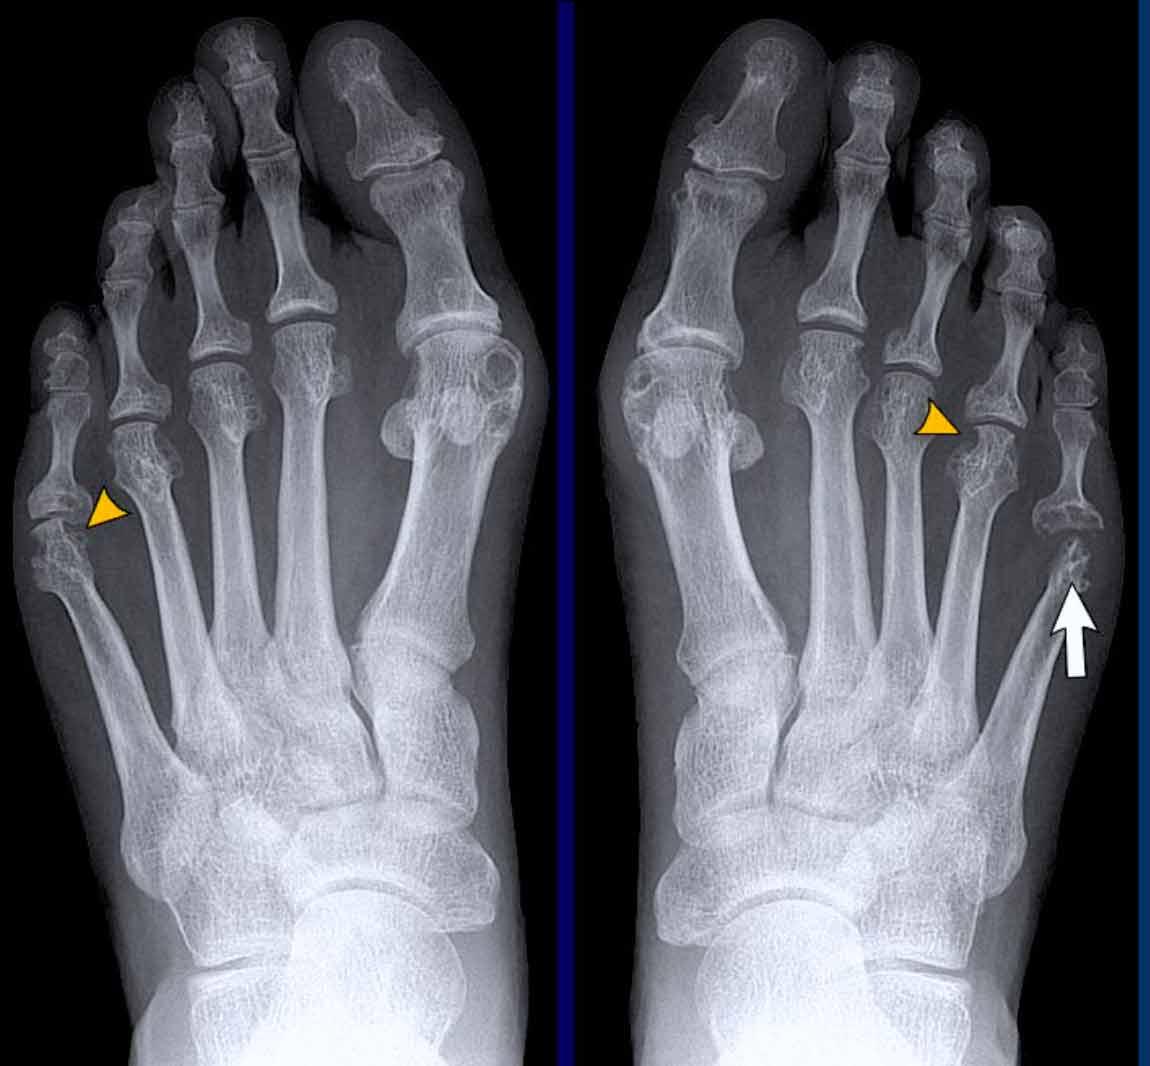

Trong trường hợp viêm khớp dạng thấp này, có hình ảnh bào mòn xương vùng rìa liền kề với hầu hết các khớp bàn ngón chân (MTP) (đầu mũi tên).

Khớp MTP thứ 5 là khớp bị tổn thương thường xuyên nhất trong viêm khớp dạng thấp.

Khi tình trạng bào mòn nặng nề như trong trường hợp này, hình ảnh có thể trông giống biến dạng “bút chì trong cốc” (mũi tên trắng) – dấu hiệu thường gặp trong viêm khớp vảy nến.

Tuy nhiên, phân bố tổn thương chủ yếu ở các khớp MTP và ít ảnh hưởng đến các khớp liên đốt là dấu hiệu gợi ý đây là trường hợp viêm khớp dạng thấp.

A. Biến dạng bút chì trong cốc tại ngón chân thứ 1 và thứ 5.

B. Tiêu xương đầu ngón (acro-osteolysis) với tiêu xương chỏm đốt ngón xa của ngón 2-4 và 5.

Có bào mòn xương tại khớp bàn ngón chân (MTP) 2 và 3.

Lưu ý hình ảnh viêm màng xương mờ nhạt tại đốt ngón xa của ngón 1 bên phải (đầu mũi tên).

Có các bào mòn xương nhỏ tại chỏm đốt ngón xa của ngón 2 và 3 bên trái (mũi tên trắng).

Bên phải ghi nhận các hình bào mòn tại nền đốt ngón gần thứ 3 và tại đầu đốt ngón gần thứ 5 (đầu mũi tên trắng).

Bên trái ghi nhận hình bào mòn tại nền đốt ngón gần thứ 3 và các thay đổi tiêu xương tại đầu đốt ngón gần thứ 1 (đầu mũi tên vàng).